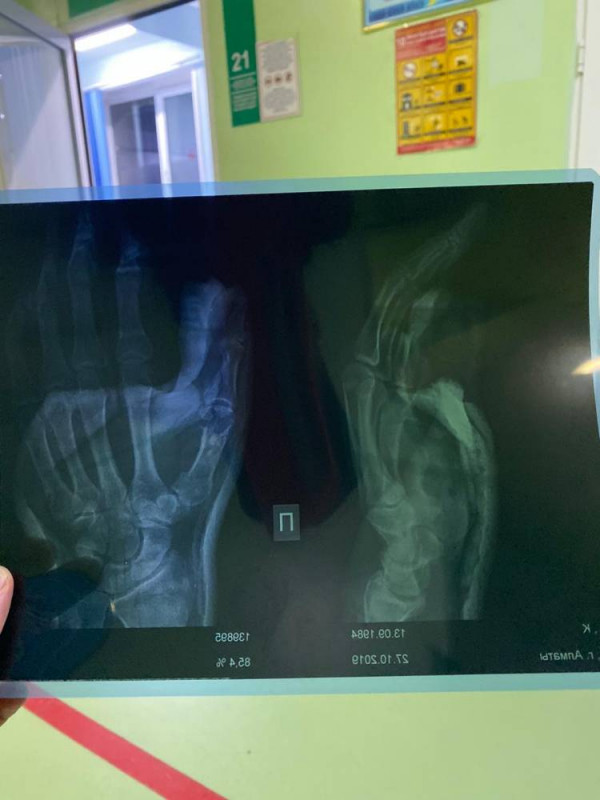

Как сообщили в команде боксера, начиная с седьмого раунда, Ислам бился со сломанной кистью правой руки. Из-за этого он не мог наносить удары по сопернику. После поединка казахстанскому боксеру наложили гипс на травмированную руку.